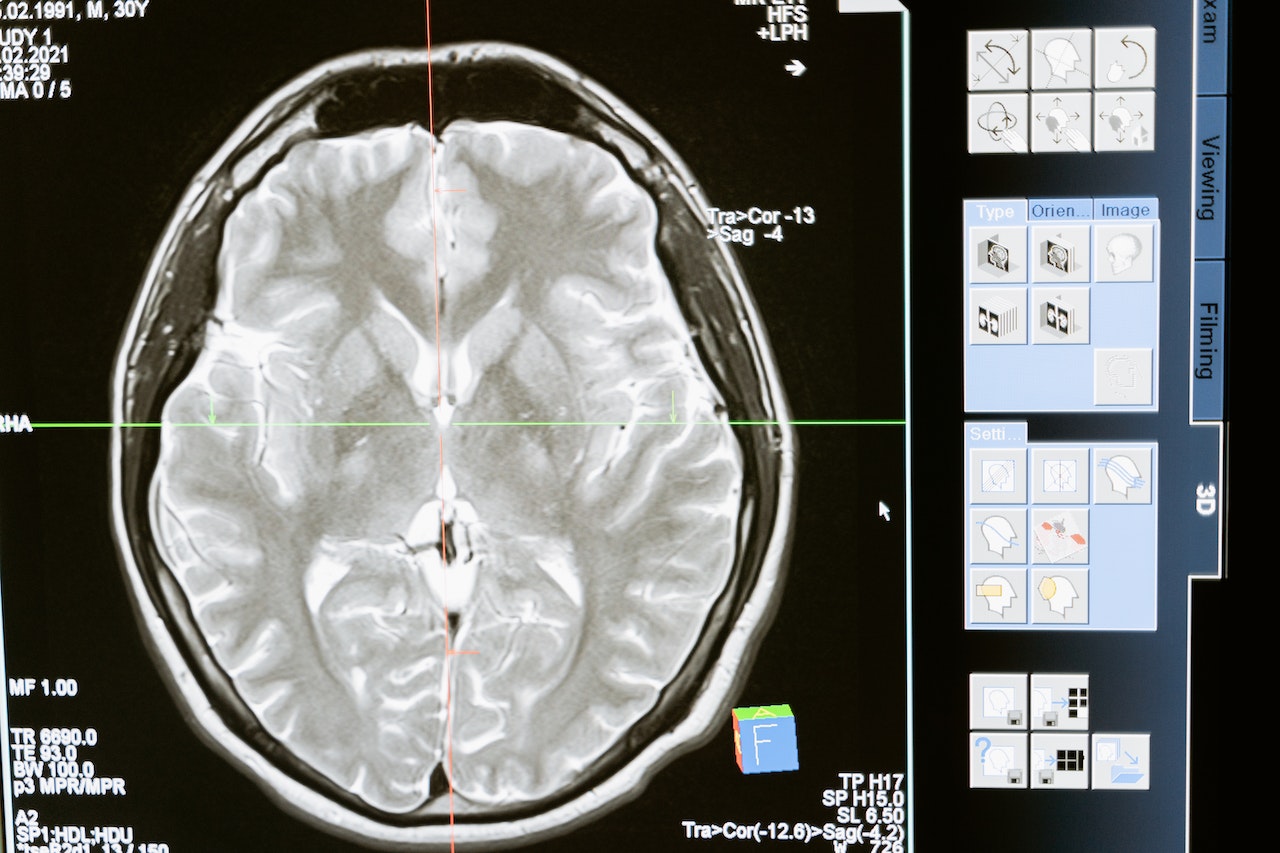

تشكل الشبكة العصبية المعقدة داخل جمجمة الإنسان كل جانب من جوانب حياته، إذ ينبع داخلها نحو 100 مليار خلية عصبية تنطلق ليل نهار. ولحسن الحظ، يوجد تأثير أكبر على بنية الدماغ وعمله مما أدركه العلم من قبل. بل يمكن تعزيز الإدراك والتنظيم العاطفي والصحة العقلية من خلال التدريب الموجه، وفقا لما ورد في سياق تقرير نشره موقع New Trader U.

توفر المرونة العصبية المفتاح – قدرة الدماغ على تجديد وتغيير وتشكيل اتصالات جديدة استجابة للتجارب والمحفزات. يعتقد العلماء أن الاتصالات العصبية على مر التاريخ قد تم إصلاحها في وقت مبكر من الحياة. ولكن كشفت الأبحاث الرائدة في الستينيات أن الدماغ يتكيف ويتعلم بشكل مستمر.

ينطبق القول المأثور "استخدمه أو اخسره" على القدرات العقلية، حيث إن ممارسة مناطق الدماغ الرئيسية تقوي المسارات العصبية الموجودة وتحفز نمو الخلايا العصبية. مع ازدياد قوة العضلات من خلال التدريب المستمر، تعمل تمارين الدماغ المستهدفة على تقوية نقاط القوة المعرفية والعاطفية.